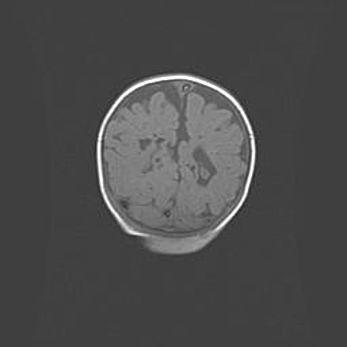

Лейкомаляция с кистозно-глиозной дегенерацией головного мозга.

Возраст: 2 месяца 25 дней

Вес: 6400 г

Окружность головы: 40 см

Срок гестации: 41 неделя

Лейкомаляцию относят к ишемически-гипоксическим повреждениям головного мозга, диагностируемым у новорожденных. При лейкомаляции в головном мозге обнаруживают очаги некроза, возникшие после тяжелой гипоксии и нарушения кровотока. В процессе морфогенеза очаги проходят три стадии: 1) развития некроза, 2) резорбции и 3) формирования глиозного рубца или кисты. Перивентрикулярная лейкомаляция (ПЛ) встречается примерно в 12% случаев среди новорожденных, обычно – у недоношенных детей, причем, частота ее зависит от массы, с которой младенец появился на свет. Наибольшее число малышей страдает лейкомаляцией, если масса при рождении 1500-2500 г.